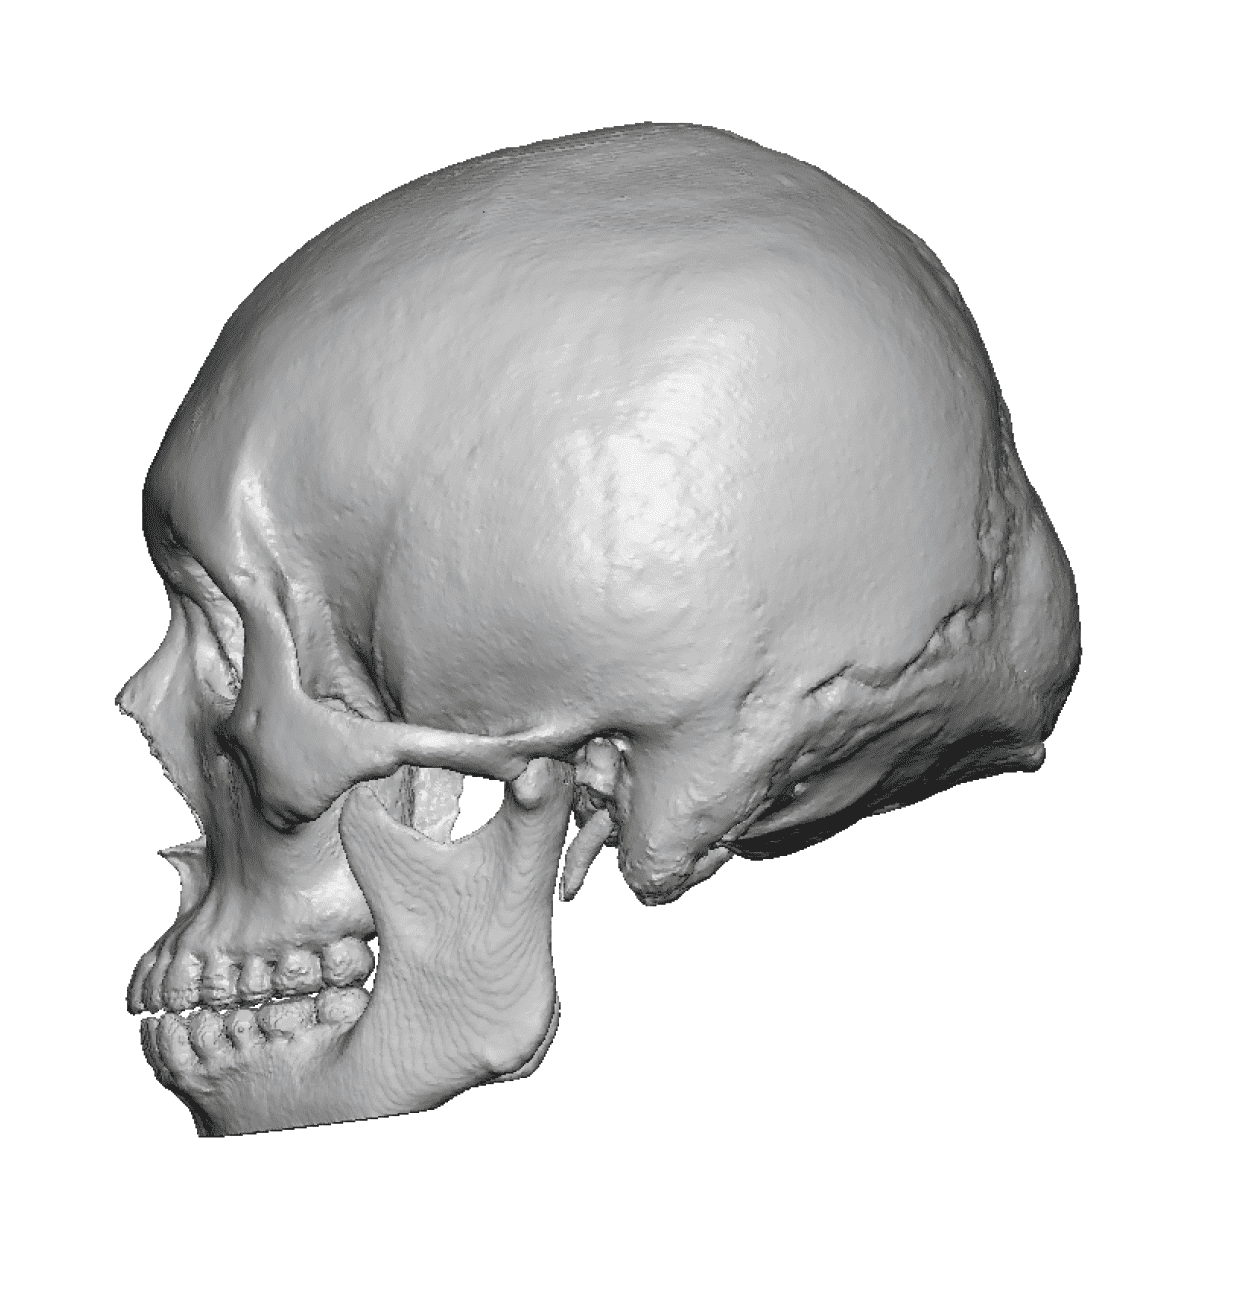

Desire for rounder shape to the top of the head from a congenital parasagittal deficiency skull shape.

Custom skull implant designed to fill in the parasagittal deficiencies.

Desire for rounder shape to the top of the head from a congenital parasagittal deficiency skull shape.

Custom skull implant designed to fill in the parasagittal deficiencies.